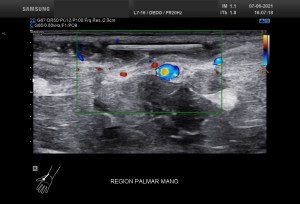

En la imagen 1 su anatomía, que es primordial y además me tiene loco perdido. El Gemelo y el Semimembranoso, profundo al Semitendinoso, que si los continuas en eje corto hacia próximal van a ser dos supermúsculos de la parte posterior del muslo. Y el cuello, del quiste que es muy bonito también.

Recuerdo la importancia de comprobar siempre la permeabilidad de los vasos del hueco poplíteo con este tipo de patologías, el parecido de los síntomas de un quiste de Baker roto y la TVP puede ser muy similar y sin embargo, la TVP es una patología potencialmente peligrosa. Para ello pide al paciente que suba la pierna afectada por encima de su otra pierna para poder hacer que el retorno venoso sea más evidente y poder estudiar los mencionados vasos, sobre todo, su vena, claro.

La compresión con la sonda del hueco poplíteo establece la permeabilidad de la vena poplitea. Normalidad por tanto, manda, el comportamiento de la vena, compresible, y no el uso del doppler, por eso me permito el lujo de enseñarte la técnica sin el uso del doppler color. Línea roja: Si la vena no se colapsa.